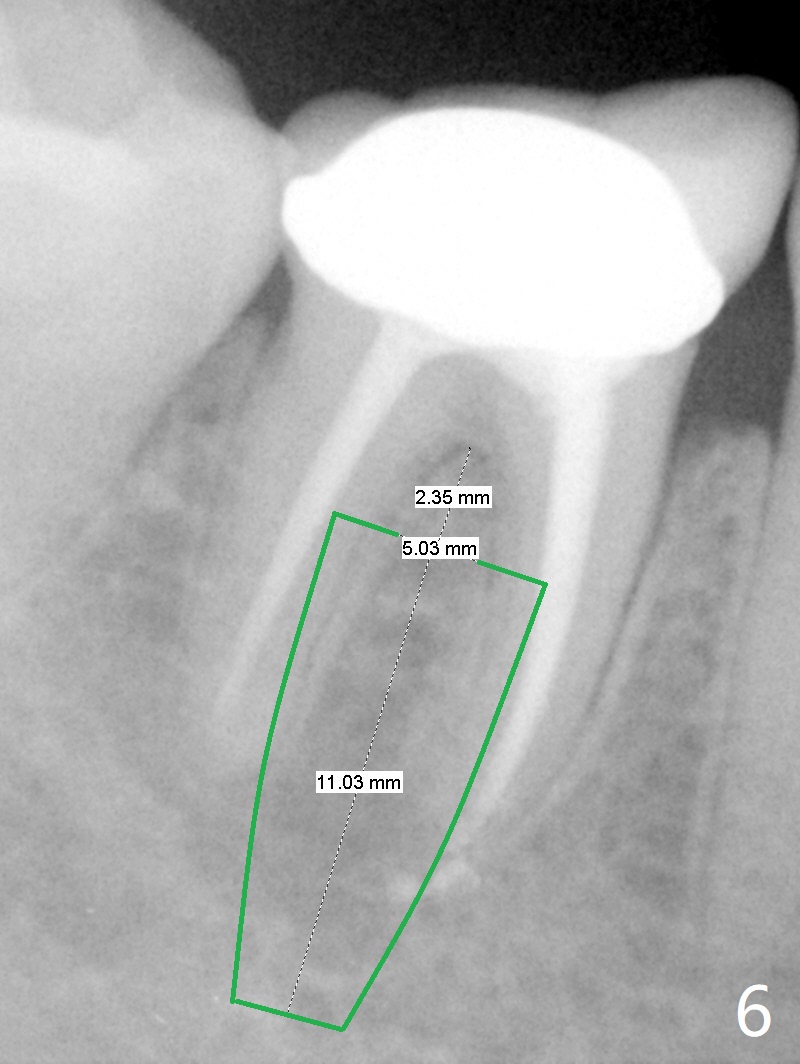

A 47-year-old woman with one carious tooth in her mouth (at #30) received RCT 14 years ago (Fig.1). The molar survives without crown for 3.5 years (Fig.2) and with crown for 8 years (Fig.3). The tooth has 2nd decays 10 years post crown (14 years post RCT, Fig.4 *). The crown dislodges 2 months later (Fig.5). Does the crown inadvertently reduce the longevity of the tooth simply hampering oral hygiene? After osteotomy until 4.5x10 or 13 mm IS drill with guide and 5 mm Bicon reamer free hand, place either 5x6 or 11 mm Bicon implant (Fig.6). Keep the black insertion plug to hold periodontal dressing or a provisional, which will be bonded to the neighboring tooth. Prepare PRFx1 for sticky bone around the not-so-stable implant. A 5x11.5 mm bone-level implant is planned by CT (Fig.7). Socket shield will be conducted to reduce buccal plate collapse. If the osteotomy depth is 10 mm due to limited mouth opening, place 4.5x6 mm Bicon implant. Otherwise 4.5x8 mm one. Return to Lower Molar Immediate Implant, Prevent Molar Periimplantitis (Protocols, Table), Trajectory II, Metronidazole Early Intervention Xin Wei, DDS, PhD, MS 1st edition 09/01/2019, last revision 11/10/2019